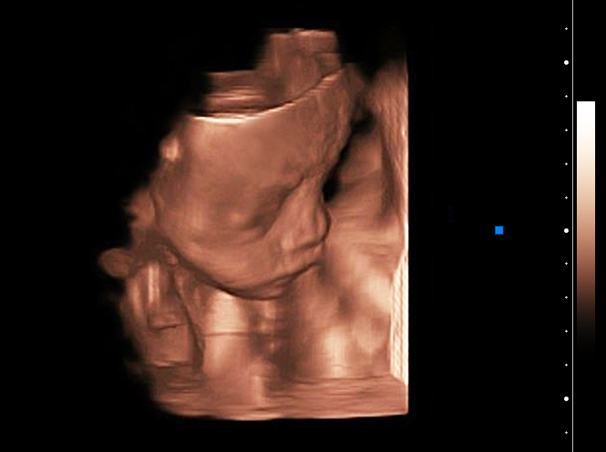

Cardiac

Four Chambers View,B BC Mode